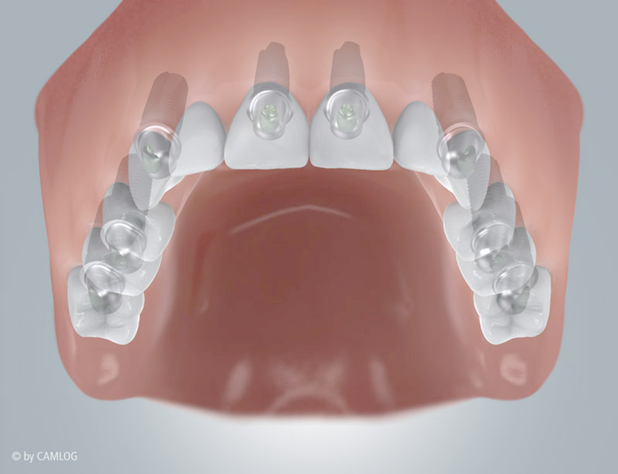

Viele Zähne fehlen

Das Leben hinterlässt Spuren, auch an den Zähnen: Die eine oder andere Lücke wird größer oder ein älterer Zahnersatz führt zu Problemen. Implantate lassen Ihre Zahnreihen wieder völlig unversehrt aussehen. Mit Einzelzahnimplantaten können Sie besonders elegant die ursprüngliche Situation wiederherstellen. Denn jeder Zahn wird separat ersetzt. Fehlen mehrere Zähne nebeneinander, können Sie sich auch für eine implantatgetragene Brücke entscheiden. Egal, welche Lösung Sie bevorzugen, die neuen Zahnwurzeln übernehmen zuverlässig die Aufgaben Ihrer natürlichen Vorgänger. Eine individuell angefertigte Krone oder Brücke schließt jede Lücke passgenau und ästhetisch einwandfrei – ohne Unterschied zu Ihren ursprünglichen Zähnen.

Befund:

Bereits einige Zähne verloren:

Ideale Version

Alle Zähne werden mit je einem Implantat ersetzt.

Alternative Version:

Manche Zähne werden mit einem Implantat ersetzt.

Implantate sind eine rundum gelungene Lösung – makellos, dauerhaft und zuverlässig. Gesunde Zähne bleiben grundsätzlich unberührt und müssen nicht wie bei einer festsitzenden Brücke abgeschliffen werden. Auch wenn am Ende einer Zahnreihe eine Lücke entsteht – eine sogenannte Freiendsituation – sind die kleinen Hightech-Schrauben eine optimale Lösung. Denn Implantate von Camlog sind der natürlichen Zahnwurzel nachempfunden. So werden Knochen und Zahnfleisch richtig belastet und ausgeformt. Störende Befestigungsklammern wie bei herausnehmbaren Prothesen sind nicht notwendig. Implantate können Ihnen sofort nach dem Entfernen von Zähnen, aber auch zu jedem späteren Zeitpunkt eingesetzt werden. Besteht eine Zahnlücke schon länger, kann der Knochen durch fehlende Belastung eventuell zu dünn oder flach geworden sein, um ein Implantat aufzunehmen. Dann kann er mit körpereigenem Gewebe oder einem knochenähnlichen Material wieder aufgebaut werden.